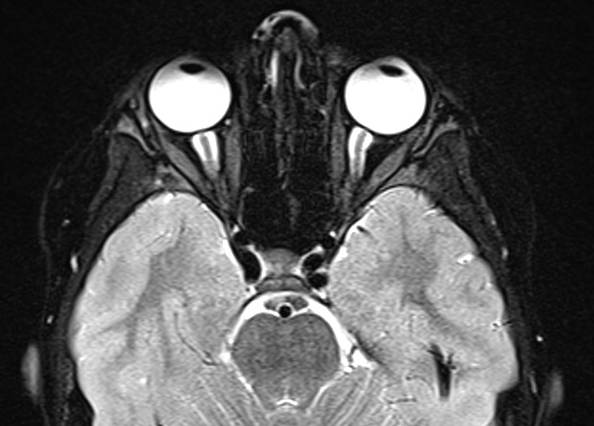

Because of the patient’s persistent severe headache, computed tomography (CT) scanning of the head was performed, which revealed small cerebrospinal fluid (CSF) spaces and low-lying cerebellar tonsils. Magnetic resonance imaging (MRI) of the brain with and without contrast similarly demonstrated low-lying tonsils and prominence of CSF within the optic nerve sheaths bilaterally, suggesting the possibility of idiopathic intracranial hypertension (IIH) (Figures 1 and 2).

Figure 2. T2-weighted fat-saturated MRI, axial view, demonstrating posterior scleral flattening and prominent optic nerve CSF spaces.